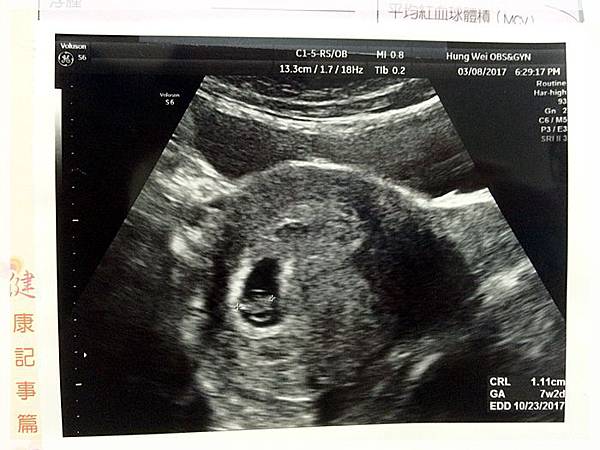

這是第一次產檢時的超音波相片...

這是第二次產檢時的超音波相片...

這是第三次產檢也就是這次產檢時的超音波相片...

歡迎你的到來...樂樂![]()